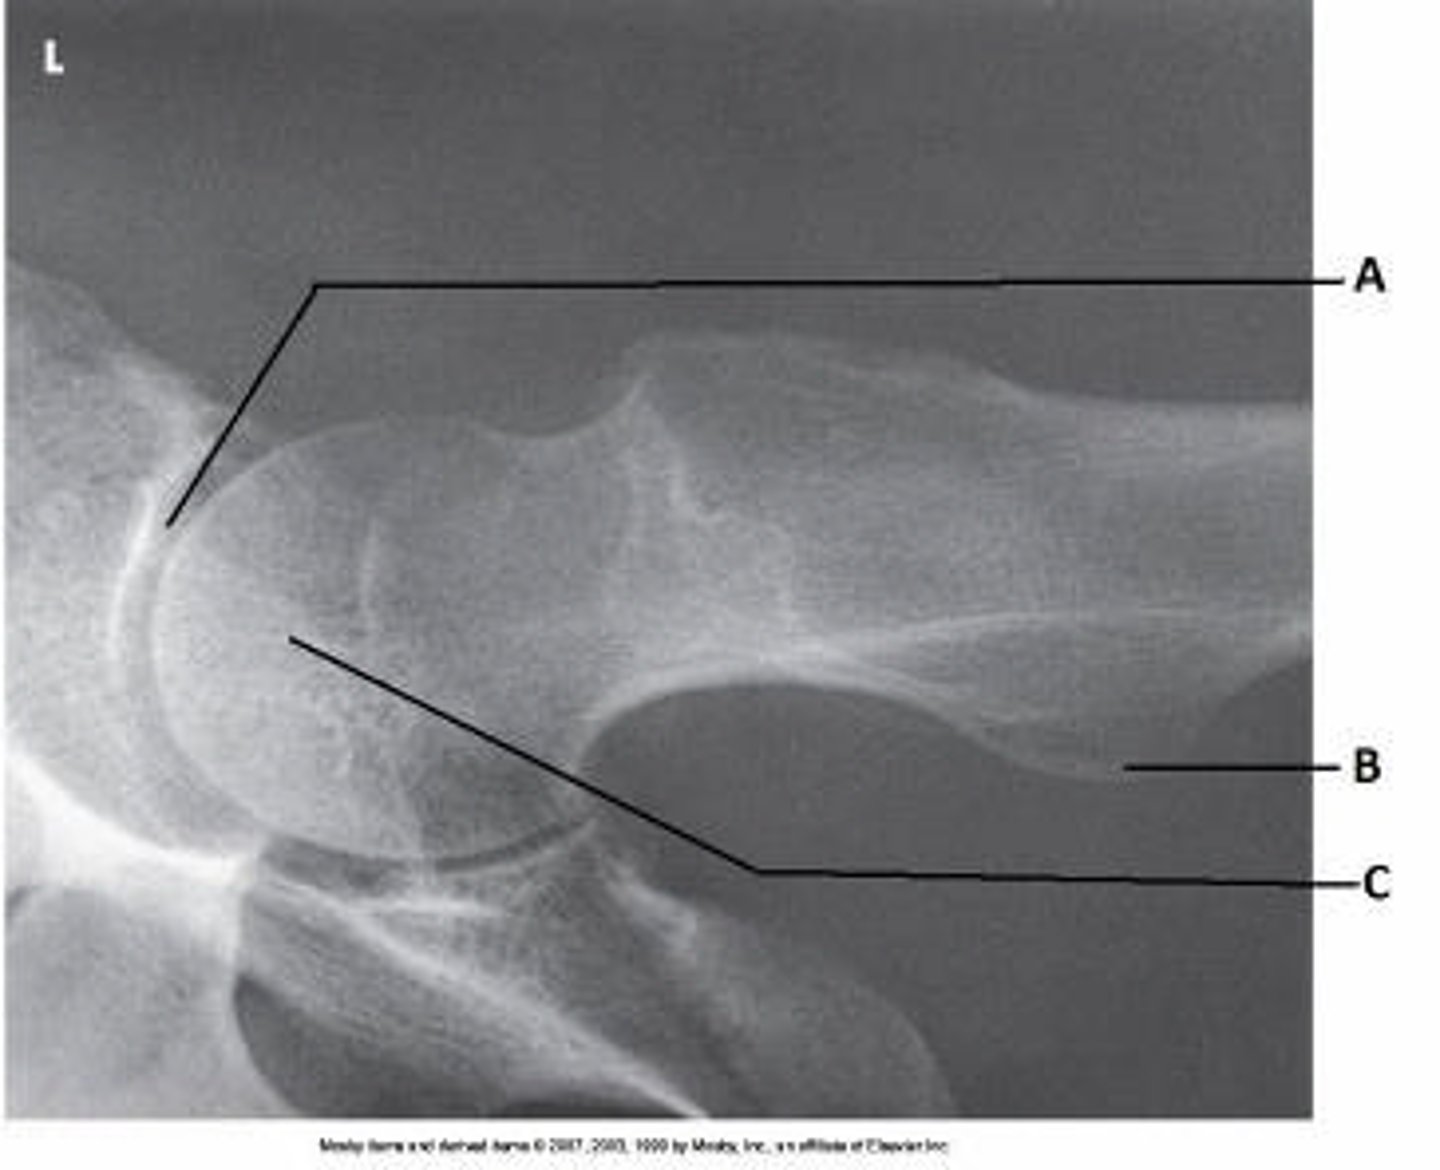

Axiolateral (Danelius-Miller)

What projection (method) is demonstrated in the image below?

Lesser trochanter

What anatomy is labeled as letter B in the image below?

Acetabulum

What anatomy is labeled as letter A in the image below?